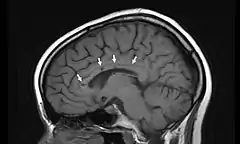

Vista lateral de una resonancia magnética nuclear de la cabeza. Las flechas indican la localización de microinfartos cerebrales característicos del síndrome de Susac.